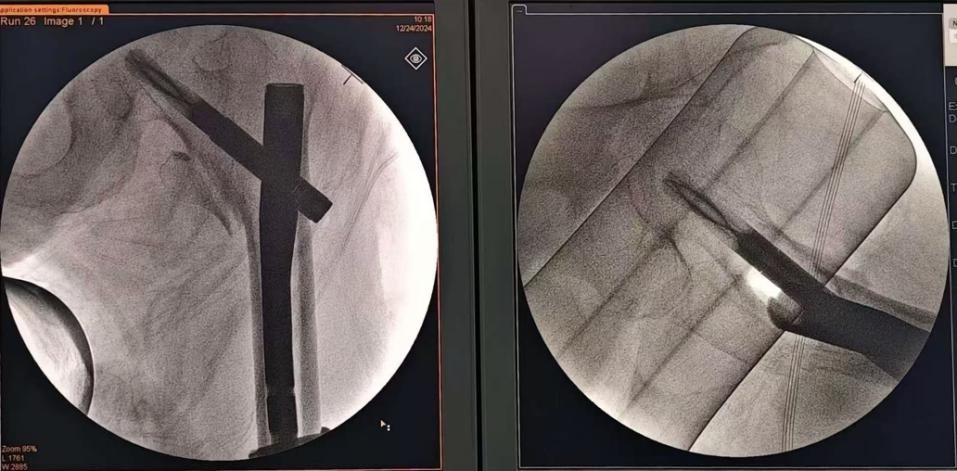

麻醉科医师顺利实施全麻后将庄老太太置于牵引床上,姜为民主任仔细小心地进行复位,达到满意的位置后。为了尽可能缩短手术时间,姜主任与助手陈唐医生穿上沉重的铅衣,在C臂机的帮助下,手术顺利完成,耗时约35分钟。术后老人家各项生命指标良好,术后首日老人家于ICU监护,第二天即回到了骨科病房。经过骨科医护团队的精心护理,目前庄老太太恢复良好,患者家属脸上的愁云也消散了。